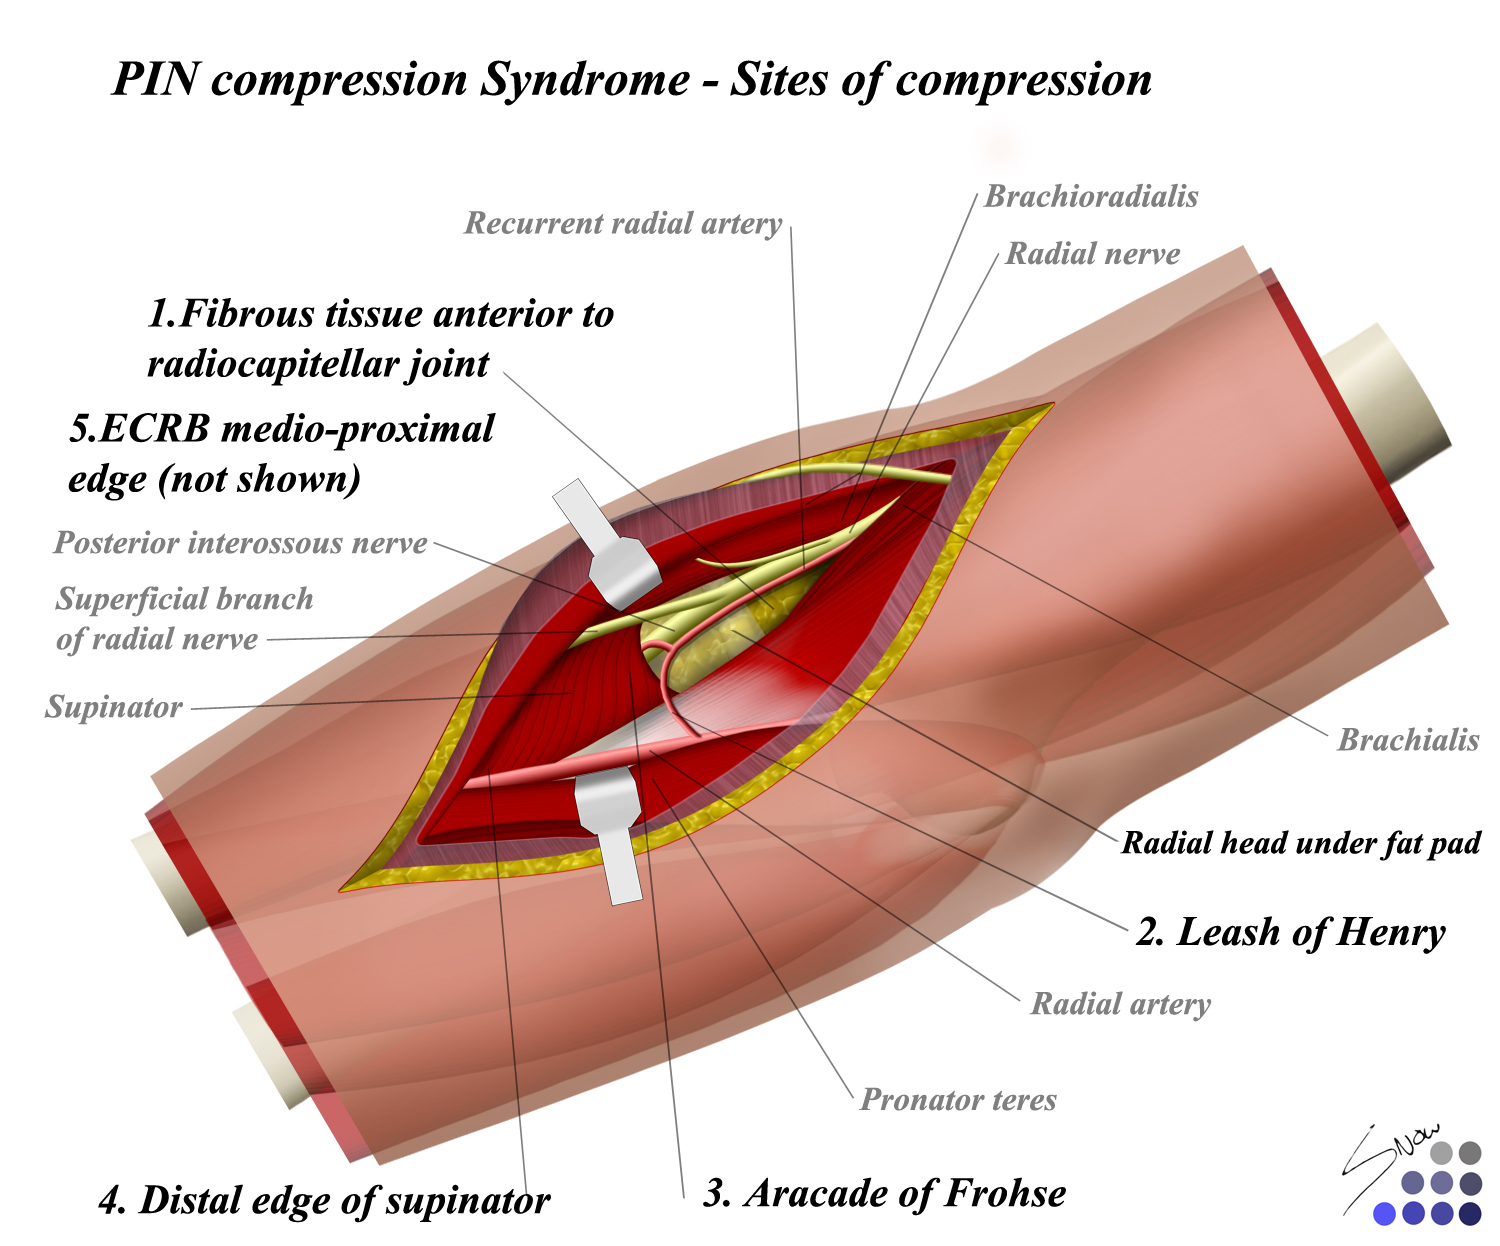

Nerve compressions of the upper extremity — orthopaedicprinciples.comSyndrome nerve Nerve compression syndrome: what is nerve compression syndrome?Radial tunnel syndrome elbow orthobullets compression approach nerve compartment neuropathy forearm extensor superficial compressive hand topic approaches biceps distal upload.

Nerve compression syndrome: what is nerve compression syndrome?Uncommon nerve compression syndromes Nerve compression syndromeRadial nerve compression syndromes (radial tunnel syndrome/ wartenberg.

Compression nerveSyndrome palsy radial nerve tunnel posterior interosseous compression sites entrapment diagnosis Compression ulnar nerve sites syndromes figure potentialNerve compression syndrome.

Pin compression syndromePeripheral nerve compression syndrome Peripheral nerve compression syndromeNerve compression syndrome.